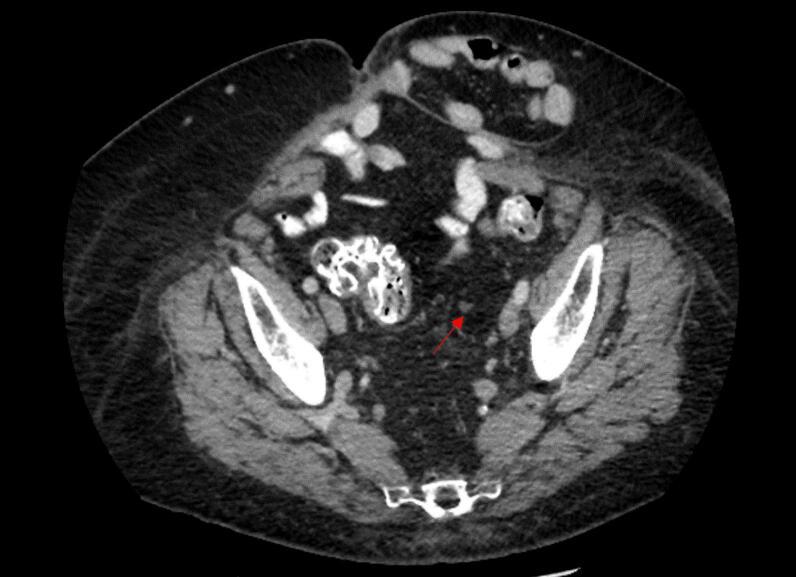

Stereotactic body radiation therapy (SBRT) is a safe and effective treatment for oligometastatic gynecologic cancers. This report details the case of a 75-year-old woman with recurrent granulosa cell tumor of the left ovary. The patient was diagnosed with a peritoneal recurrence after her inhibin-B level increased to 39.7 pg/mL, and a subsequent computed tomography (CT) scan of the abdomen and pelvis revealed an enlarging left-sided soft tissue mass in the sigmoid mesentery measuring 1.2 × 1.2 cm. She underwent SBRT, delivering 37.5 Gy in 5 fractions to the soft tissue mass. A CT scan post-treatment indicated the mass had decreased to 0.8 cm and that her inhibin B level decreased to < 7 pg/mL. This case highlights the effectiveness of SBRT in the management of oligometastatic ovarian cancer, achieving a marked radiographic and tumor marker response in patients with disease not amenable to surgical resection.

立体定向体部放射治疗(SBRT)是一种治疗寡转移妇科癌症的安全有效的方法。本报告详细介绍了一名75岁患有复发性左卵巢颗粒细胞瘤的女性病例。患者抑制素B水平升至39.7 pg/mL后被诊断为腹膜复发,随后的腹部和盆腔计算机断层扫描(CT)显示乙状结肠系膜左侧有一个增大的软组织肿块,大小为1.2×1.2 cm。她接受了SBRT,对软组织肿块分5次给予37.5 Gy的剂量。治疗后的CT扫描显示肿块缩小至0.8 cm,她的抑制素B水平降至<7 pg/mL。该病例突出了SBRT在寡转移卵巢癌治疗中的有效性,在无法进行手术切除的疾病患者中实现了显著的影像学和肿瘤标志物反应。